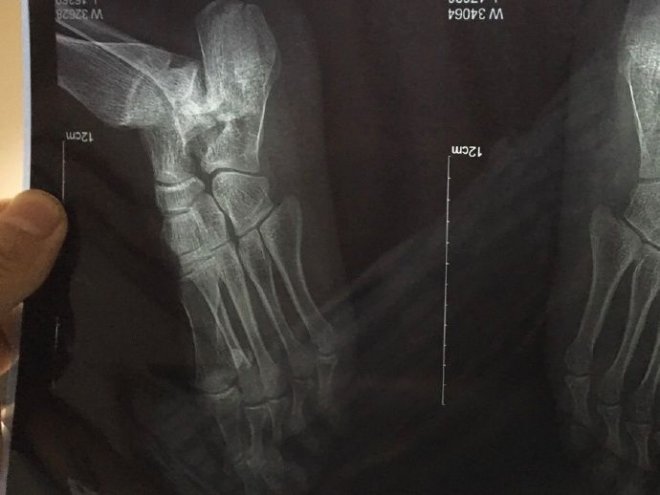

感受過200斤胖子在你身上蹦嗎?後來小姐累了,直接往原PO腿上一躺,瞬間他麻痺失去知覺,痛到當場哭了,小姐也嚇得不輕不知道發生什麼事。原PO請她快幫忙穿衣服,並打電話叫救護車。然後他就這樣出差沒辦事躺進了醫院,拍片才發現自己

骨折了!